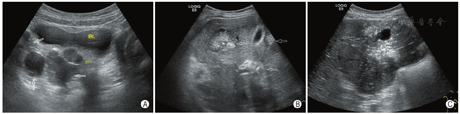

病例4,男,10岁3个月,因间歇性腹痛3周,当地医院发现腹部多发占位,行穿刺活检,术后病理考虑促结缔组织增生性小圆细胞瘤肿瘤来诊,基因检测显示EWSR1(22q12)基因断裂。超声检查可见盆腔、腹腔肠系膜、大网膜、肠壁、肝脏、肝包膜、脾脏、膈肌、膀胱壁、肠壁、左肾、后腹膜等部位多发大小不等低回声包块,形态不规则,表面分叶状,较大包块可见多发钙化斑及液化区,部分包块互相融合,包块最大者位于肝左叶,长径18.3 cm,凸向肝外生长(图4)。胸部CT提示右肺胸膜多发块状、结节状软组织密度影,考虑肿瘤转移灶。来院后开始规律化疗,每隔1个月定期超声随访,目前共随访3个月,肿瘤有所缩小。